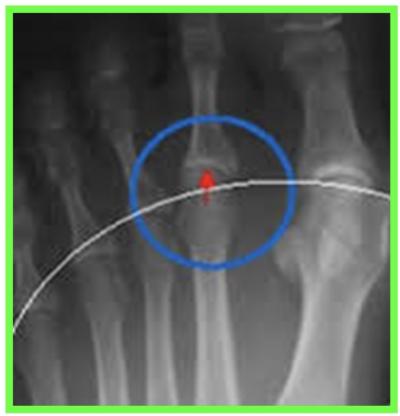

SYNDROME DU 2 EME RAYON :

Le Syndrome du 2ème rayon est un syndrome douloureux dû à une surcharge mécanique sur l’articulation métatarso-phalangienne du 2éme orteil.

L’évolution se fera par la suite vers une déformation progressive du 2éme orteil

En fonction de l’importance de la lésion de la plaque plantaire (fissure simple ou complexe, déchirure), cela crée une déviation de l’orteil, perte d’appui, chevauchement d’orteils, apparition d’une « griffe », dislocation articulaire métatarso-phalangienne.

RADIOGRAPHIE DU PIED EN CHARGE F + P, ECHOGRAPHIE

IRM : Bursite , rupture de la plaque plantaire